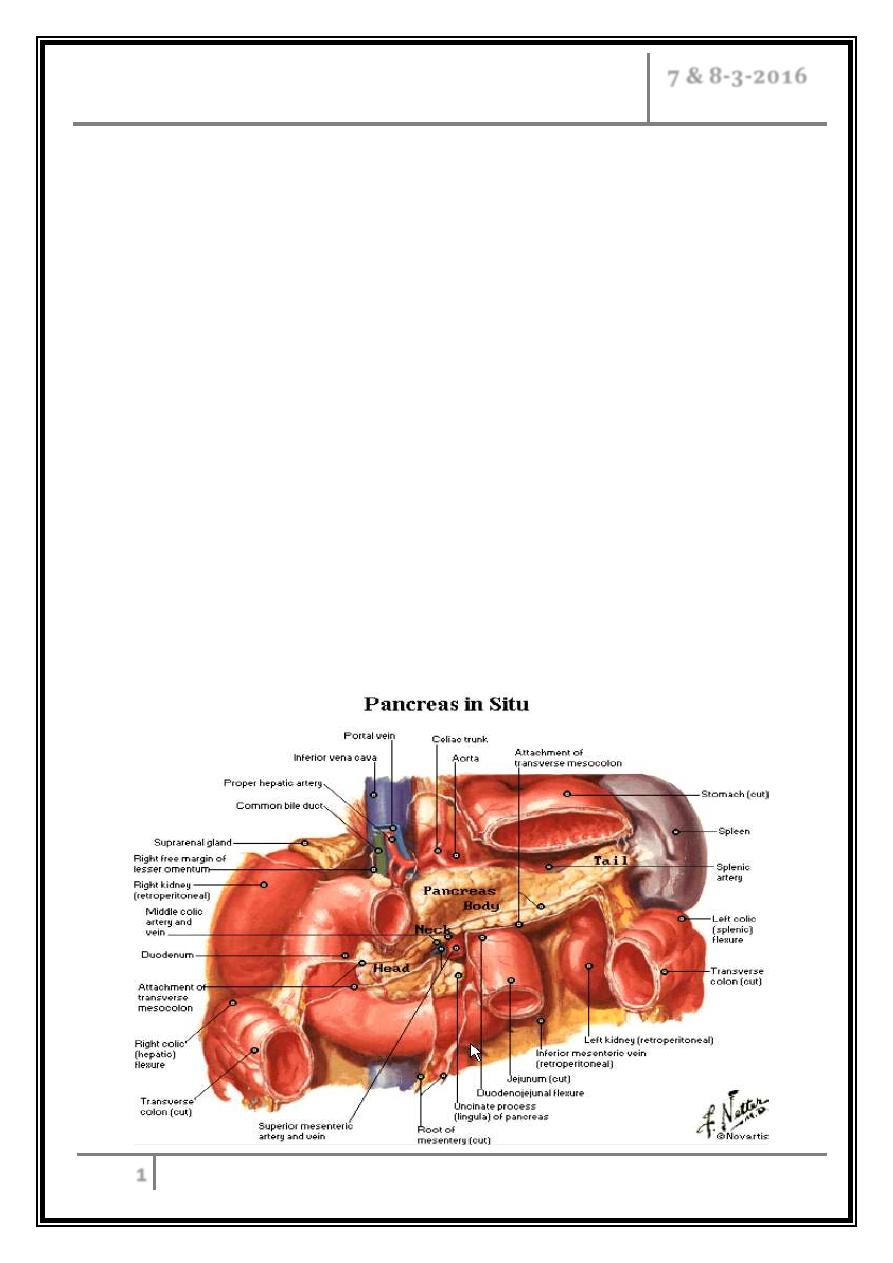

The pancreatic STRUCTURE AND FUNCTION

Extends retroperitoneally across the posterior abdominal wall from the second

part of the duodenum to the spleen.

The head is encircled by the duodenum; the body, which forms the main bulk of

the organ, ends in a tail that lies in contact with the spleen.

The pancreas consists of exocrine and endocrine cells making up 98% of the

human pancreas.

The pancreatic acinar cells are grouped into lobules forming the ductal system

which eventually joins into the main pancreatic duct.

The main pancreatic duct has many tributary ductules and gradually tapers

towards the tail of the pancreas.

The main pancreatic duct itself usually joins the common bile duct to enter the

duodenum as a short single duct at the ampulla of Vater.